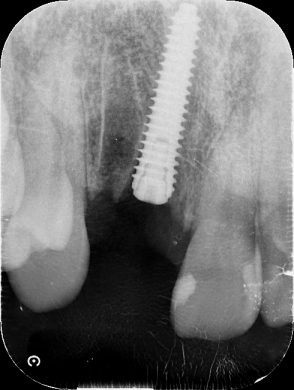

使用インプラントの特徴

本症例では、メガジェン社の「AnyRidge(エニリッジ)」を使用しました。

このインプラントは

- 高い初期固定を得やすい構造

- 骨への適応性に優れる設計

- 即時荷重に適した性能

を有しています。

本症例における臨床指標

■ インプラント長:18mm

皮質骨に確実に到達し、安定性を確保

■ 埋入トルク:80Ncm以上

即時荷重基準を大きく上回る高い初期固定

■ ISQ値:78

客観的に見ても高い安定性を示す数値

精度を支える技術:デンサーバー

本症例では、骨形成に

デンサーバー(Densah Bur)

を使用しています。

この技術により

- 骨を削るのではなく圧縮・緻密化

- 骨密度の向上

- 形成精度の向上

が可能となり

👉 初期固定の質をさらに高める結果につながります。